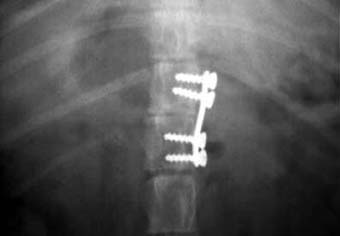

他院からの依頼症例

犬の脊椎骨折。

脱走してしまい、動けなくなっていたところを保護されました。

第13胸椎と第1腰椎の部分で骨折していました。

写真上段: 手術前

写真中段: 手術後 側面像

写真下段: 手術後 腹背像

海綿骨スクリューというネジ山の深い骨ネジと小型プレートで固定整復しました。

プレートによる整復固定で痛みは無くなりましたが、後駆麻痺は改善しませんでした。 |